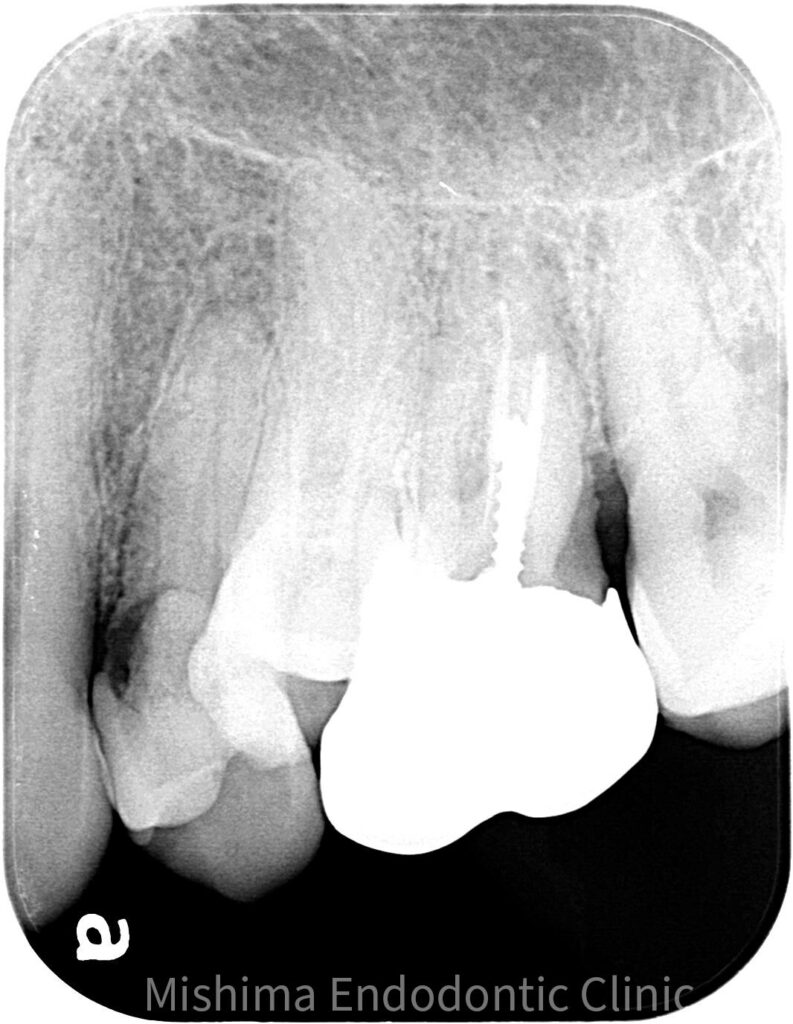

Before

| 治療内容 | 左上4が歯頚部よりカリエスを認めた。歯肉縁下カリエス、かつ、左上5の口蓋側への捻転により衛生管理が困難なため、左上4を抜歯し、左上5を保存することとした。 矯正は希望されなかったため、5→4に自家歯牙移植を行なった。 |

術前